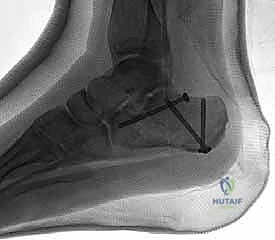

5. التثبيت النهائي باستخدام الشرائح والمسامير (Plating)

يتم وضع شريحة تيتانيوم (Titanium Plate) مصممة خصيصاً لتطابق الشكل التشريحي لعظم الكعب. يتم تثبيت هذه الشريحة بمسامير قوية لتوفير ثبات ميكانيكي صلب يسمح بالالتئام السليم ويمنع انهيار العظم مرة أخرى. في بعض الحالات التي يوجد فيها فراغ عظمي كبير، قد يستخدم الدكتور هطيف طعوماً عظمية (Bone Grafts) لملء الفراغ.

توضح الصور التالية مدى تعقيد الجراحة والدقة التي يتطلبها تثبيت عظم الكعب، والتي يعكسها التميز الجراحي للأستاذ الدكتور محمد هطيف: